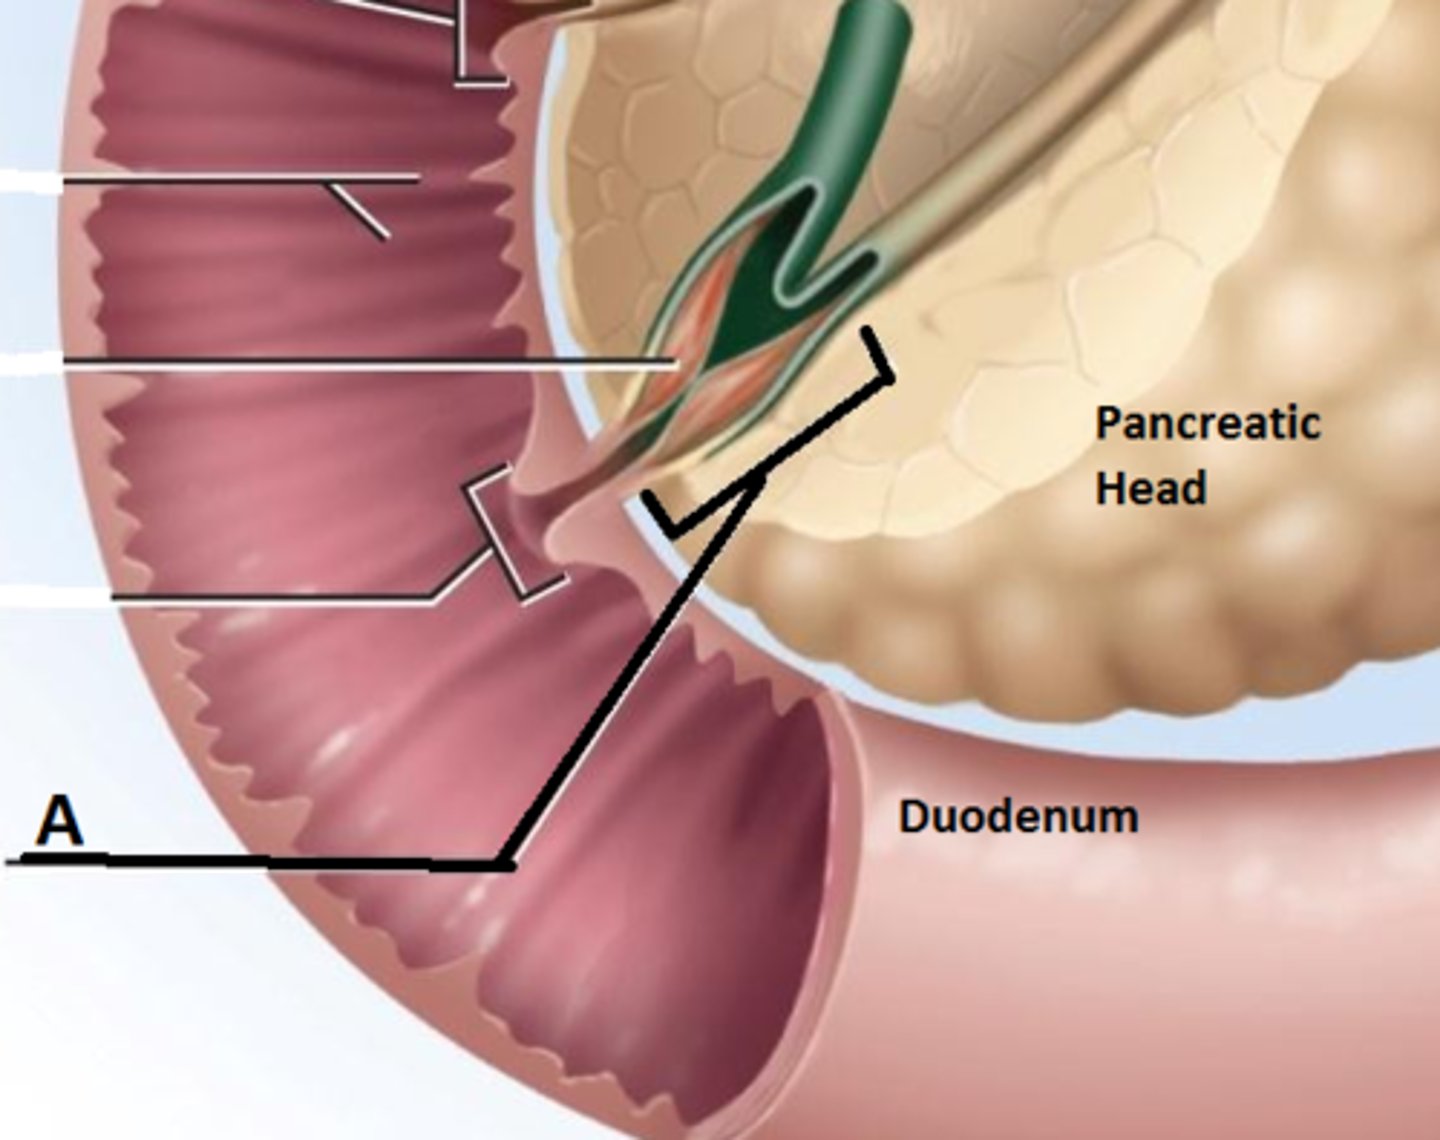

duodenum

major duodenal papilla

opening of ampulla into duodenum

circular folds (duodenum)

head (of pancreas)

hepatopancreatic ampulla

pancreatic + bile duct